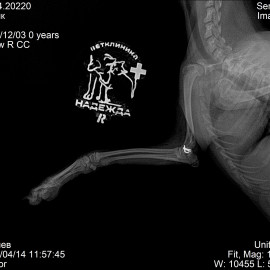

Пациент - собака по кличке Барик.

Обратились в клинику с жалобами на отсутствие опороспособности на правую переднюю лапу.

Были проведены осмотр и рентгенологическое исследование. Поставлен диагноз: перелом правого плеча. Проведена операция: остеосинтез правой плечевой кости.

Снимок 1 до операции.